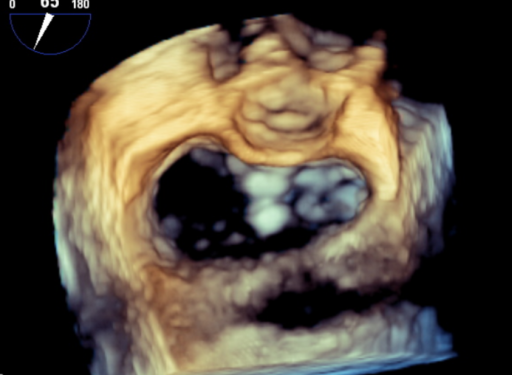

手术于全麻下进行,术前TEE提示重度功能性二尖瓣反流,反流位于A2/P2,瓣膜活动度可(图1)。手术采用经典股静脉房间隔途径,房间隔穿刺后置入24F导引导管及二尖瓣夹输送系统,在TEE引导下准确植入一枚二尖瓣夹,瓣膜夹位置稳定,植入后反流基本消失(图2),二尖瓣跨瓣平均压力阶差2mmHg,双孔化形成,遂移除器械输送系统。患者术后恢复良好,瓣膜夹位置稳定,拟于近期出院。

图2:术后TEE提示,二尖瓣夹植入后反流基本消失,双孔化形成